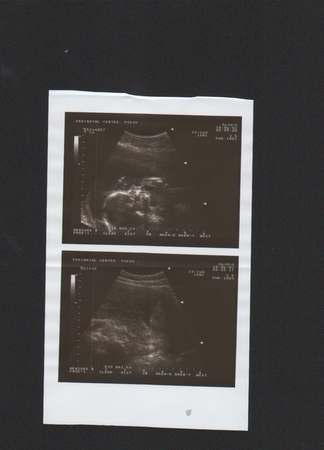

А мы были на УЗИ:)

Результаты: УЗИ, КТГ, доплера, скрининга

На верхней фотографиии и так всё понятно мы сосём пальчик

. А на нижней видно то, что мы ДЕВОЧКА

. Боже, КАК я счастлива